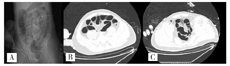

患者男,27岁,于2020年11月19日晨,被家属发现昏迷在家中(家属诉已2 d未能联系上患者),全身冰冷,四肢无活动,当时周围可见咖啡色呕吐物,室内门窗紧闭、可见烧炭的残留物,由120送入我院。查体:体温(T)36.2℃,呼吸次数(R)26次/min,血压(BP)74/35 mmHg,指氧饱和度71%。浅昏迷,巩膜及全身皮肤未见出血点,头颅无畸形,双侧瞳孔等大等圆(直径3 mm),对光反射迟钝,口唇紫绀,胸廓无畸形,双肺呼吸音粗,闻及散在湿性啰音,无胸膜摩擦音。心率(P)150次/min,律齐,未闻及杂音;全腹膨隆,腹肌稍紧张;双侧巴宾斯基(Babinski)征阴性。2020年11月19日9:00辅助检查:(1)血气分析(气管插管机械通气中、吸氧浓度FiO2:100%):酸碱度7.22、二氧化碳分压26 mmHg、氧分压154 mmHg、乳酸4.8 mmol/L、剩余碱-17.1 mmol/L、实际碳酸氢根10.6 mmol/L、COHb 16.3%。(2)血常规检查:白细胞计数19.2×109/L,红细胞计数6.43×1012/L,血红蛋白194 g/L,血细胞比容61%。(3)心肌损伤标记物检查:肌酸激酶同工酶11.2 ng/ml,肌钙蛋白1.09 ng/ml,肌红蛋白300.1 ng/ml。N-末端B型利钠肽前体15 020 pg/ml。(4)肝功能:总胆红素25.8 μmol/L,血清丙氨酸氨基转移酶137 U/L,血清天门冬氨酸氨基转移酶683 U/L,δ胆红素11.40 μmol/L。(5)凝血检查:凝血酶原时间17.0 s,国际标准化比值1.44,纤维蛋白原5.28 g/l。(6)肾功能及电解质检查:镁1.52 mmol/L,钾:3.96 mmol/L,钠147.00 mmol/L,氯108.00 mmol/L,磷2.32 mmol/L,尿素34.3 mmol/L,肌酐524.00 μmol/L,尿酸1 158 μmol/L。10:30心脏彩超检查示心脏各腔室大小正常;每搏输出量25 ml。11:00对患者头颅、胸部、腹部进行CT检查(见图1、图2):双侧基底节区片状低密度影,建议MRI检查;右下肺炎症,左下肺节段性肺不张;双肺少许纤维灶;双侧少许胸膜反应;肠梗阻。11月21日14:00下肢血管彩超:右侧股静脉、髂静脉、腘静脉管腔内异常回声,考虑漂浮血栓可能。见图3。右下肺炎症,左下肺节部他处尘肺不张,双侧少许纤维;双侧少许胸腹反应。

提示肺腔积气扩张及小液囊肠梗阻